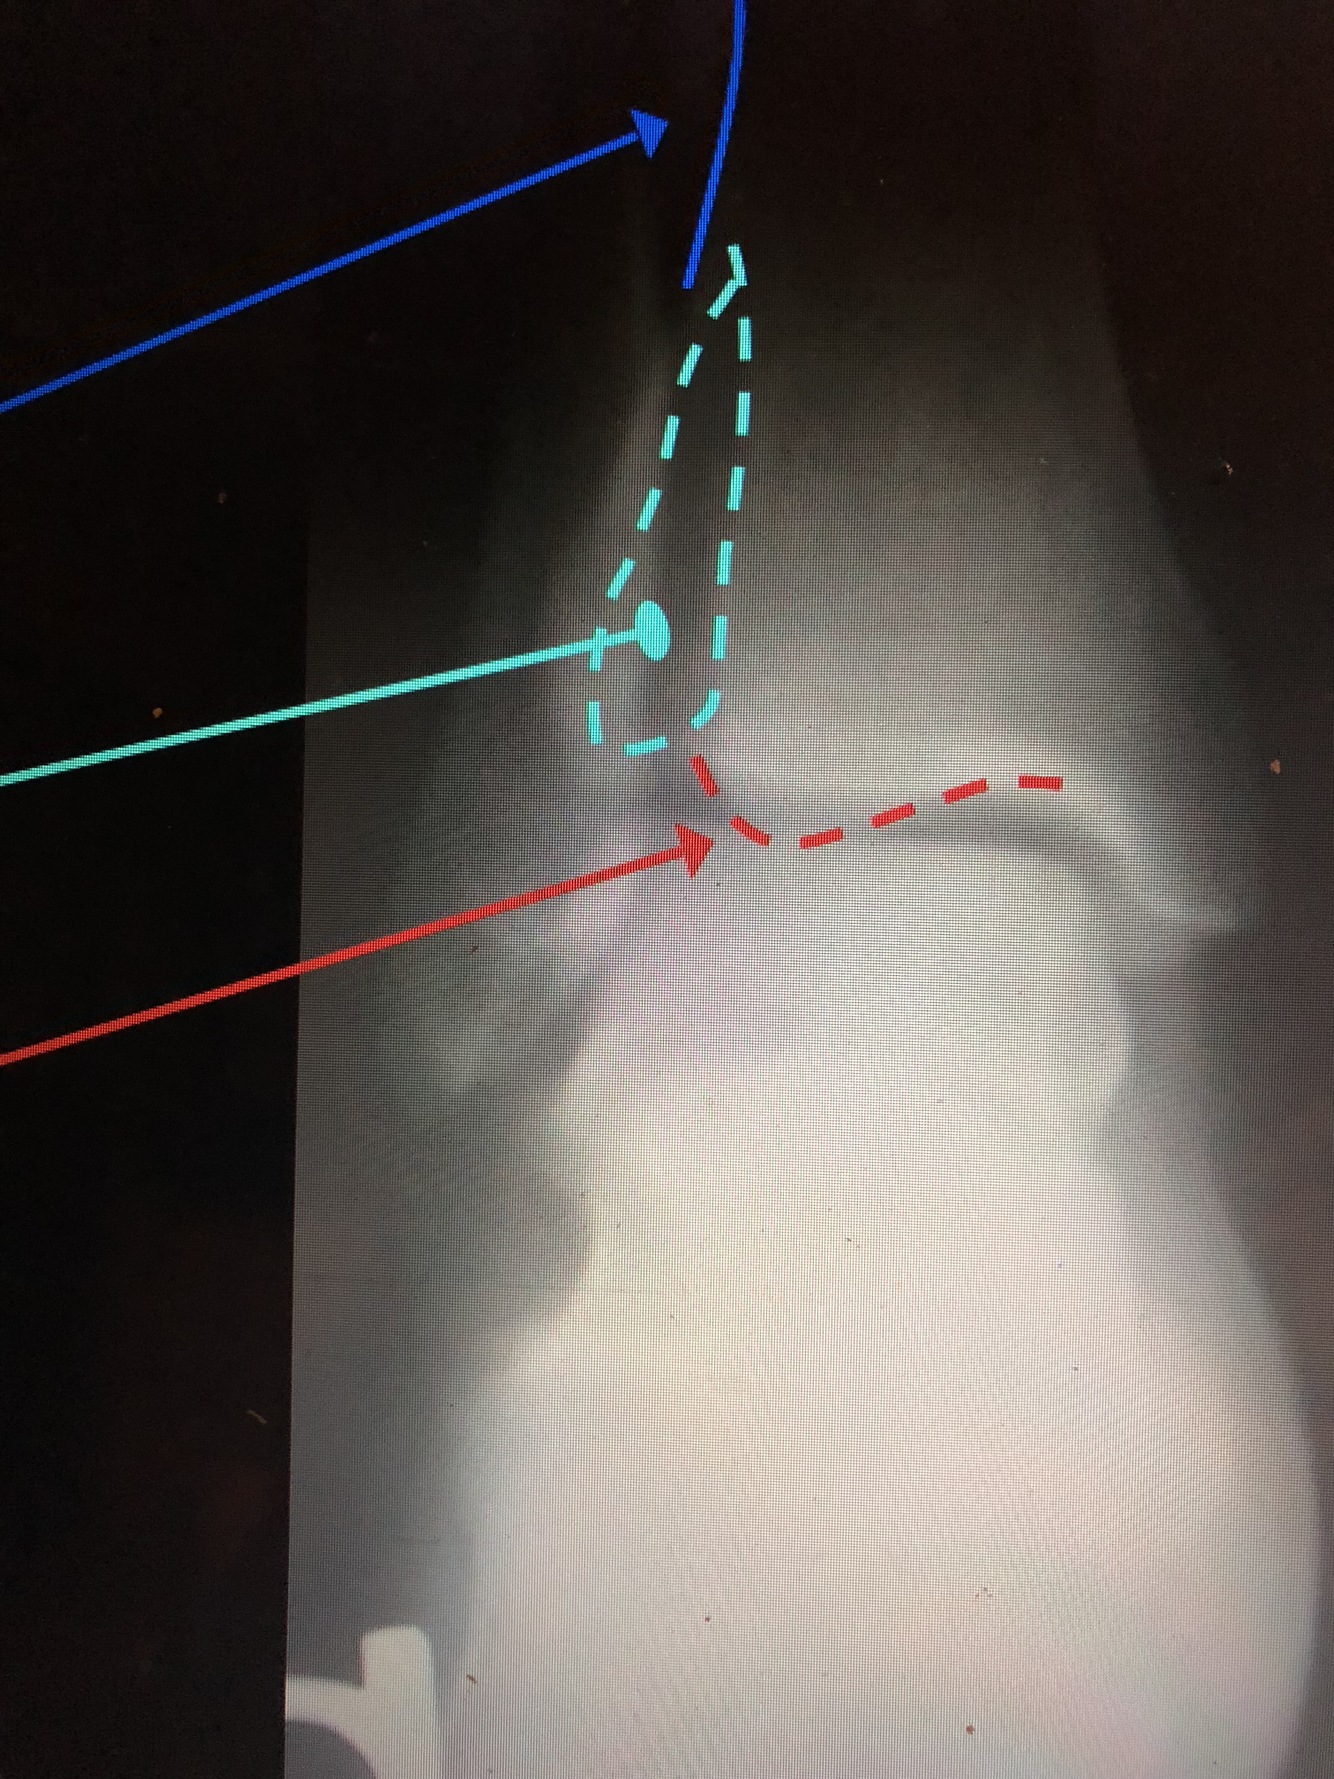

What is the dark blue line?

Interosseous Crest of the distal tibia

What is the light blue dotted line?

Fibular Notch

What is the red dotted line?

Posterior Malleolus

What is the green?

distal Fibular Shaft